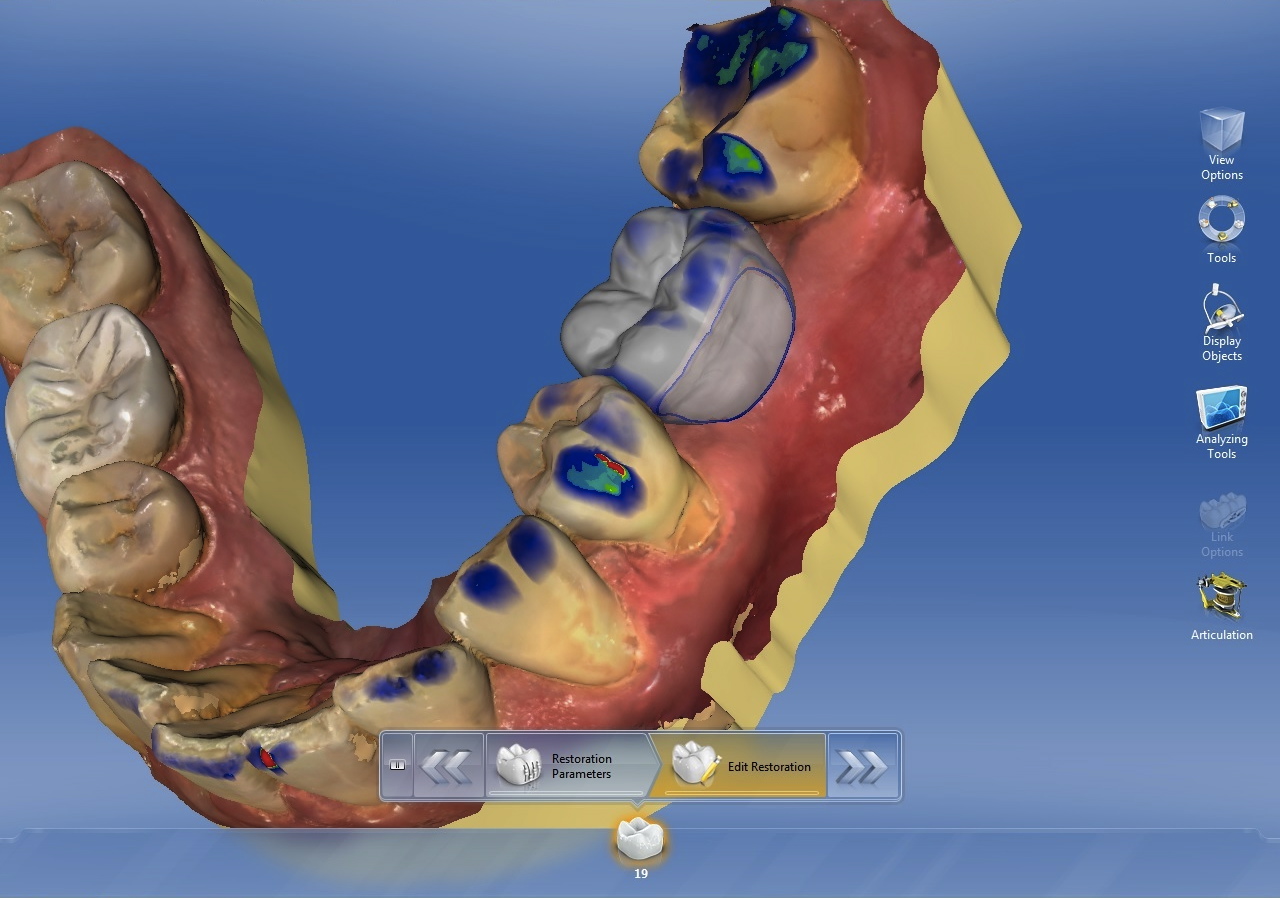

Two factors affect implant depth: distance to the proximal contact and surrounding the implant with 1 mm of bone. The implant platform should be 5 mm or less from the proximal contact for proper papilla formation.21,22 Accounting for prosthetic components, the distance to the occlusal surface should be approximately 7 mm (5 mm abutment + 2 mm ceramic). If placing the restorative platform at the osseous crest does not provide this space, it is necessary to remove bone so the implant can be submerged to proper depth. However, if placing the platform 7 mm from the restorative surface does not result in surrounding the implant with 1 mm of bone, a decision must be made. The deficiency will usually be on the facial. The practitioner must either submerge the implant until there is sufficient bone surrounding it, or if this places the implant too deeply, augment the ridge prior to implant placement. Current guided regeneration techniques can predictably gain up to 5.5 mm horizontally23 and 10 mm to 12 mm vertically.24 Once the implant platform is set, the final apical length of the implant can be adjusted and the digital plan is complete (Figure 3).

CBCT with final implant plan. Note the digital restoration, TiBase abutment, and highlighted IANB.

Figure 3